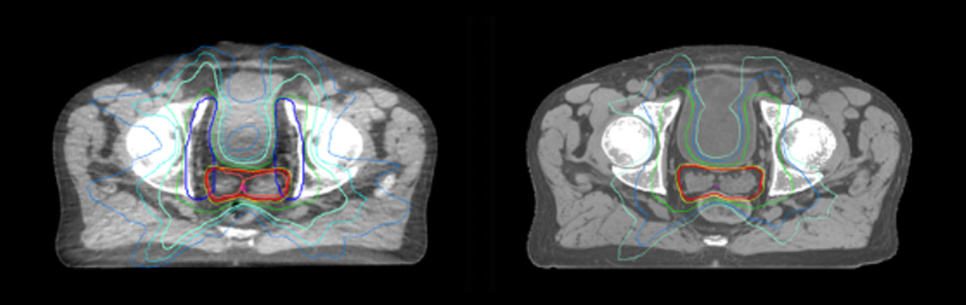

Evaluation of MRCAT dosimetric accuracy

Dosimetric equivalence validation was performed on 43 patient cases by comparing MRCAT-based dose plans overlaid on CBCT image dataset and on the corresponding MRCAT image dataset. Mr. Bolard and Dr. Champion found good agreement between MRCAT-based and CT-based dose calculations, with a mean dose ratio of 1.007 (0.991-1.014). The 3D gamma score was greater than 95% (95.2-99.0%) for all plans checked. A poster on this work was accepted for presentation at ESTRO 2020.

Dose plans overlaid on CBCT image dataset (left) and on MRCAT image dataset (right).